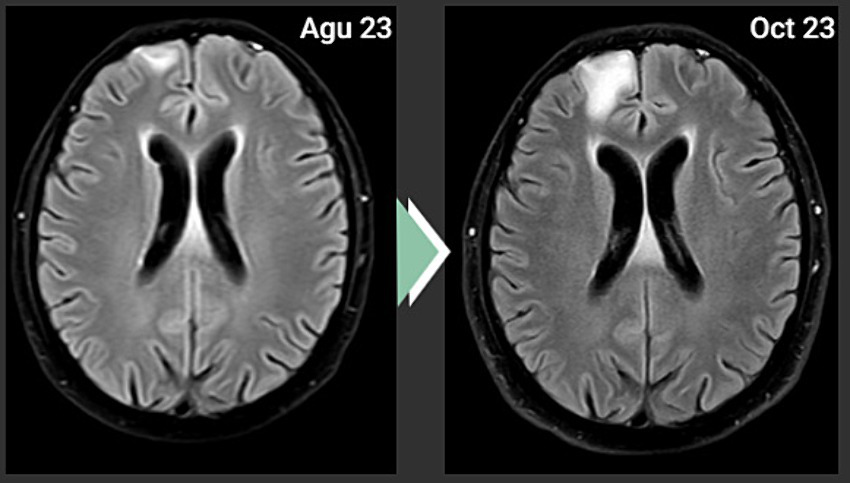

Based on the positive PD-L1 value, an off-label administration of Carboplatin + Pemetrexed + Pembrolizumab was decided. However, the cranial MRI scan after 4 cycles of this treatment showed progression (Figure 3). There was no metastatic lesion detected in the PET-CT scan for restaging purposes, other than the progressive lesion in the brain. As a second line of systemic therapy, Paclitaxel + Gemcitabine was started.

Figure 3

Cranial MRI showing progression.